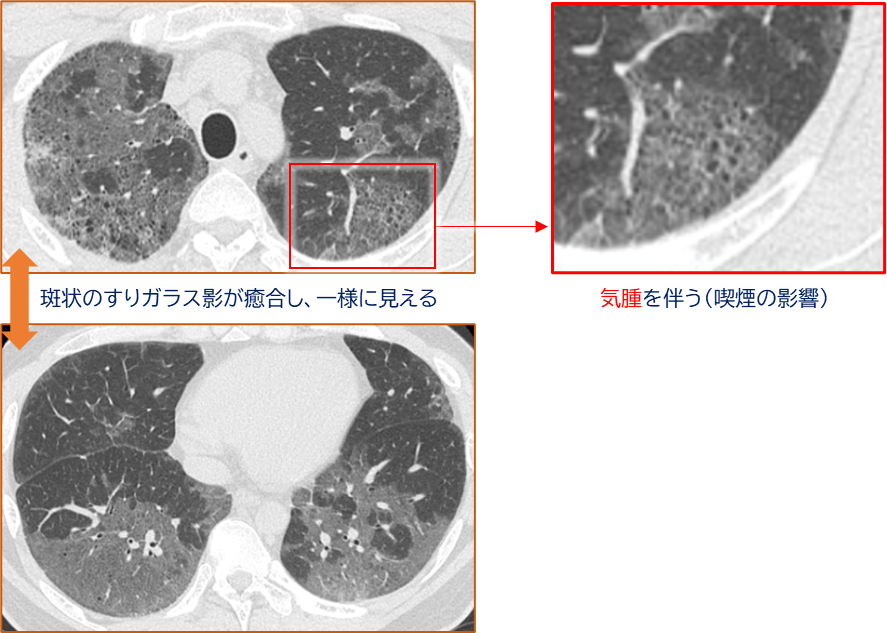

胸部CT所見

AMPの画像診断では、中下肺を中心としたすりガラス影が特徴的です。

- 分布:中下肺優位。末梢領域に優位に分布することが多い

- 形態:

- 斑状~癒合性のすりガラス影

- 平滑な網状影を伴う

- 時に嚢胞性変化や肺気腫、牽引性気管支拡張を伴う

- 蜂巣肺(honeycombing)は稀

➡ CT上の「confluent GGO(癒合性のすりガラス)」がRB-ILDとの違いを示唆します。